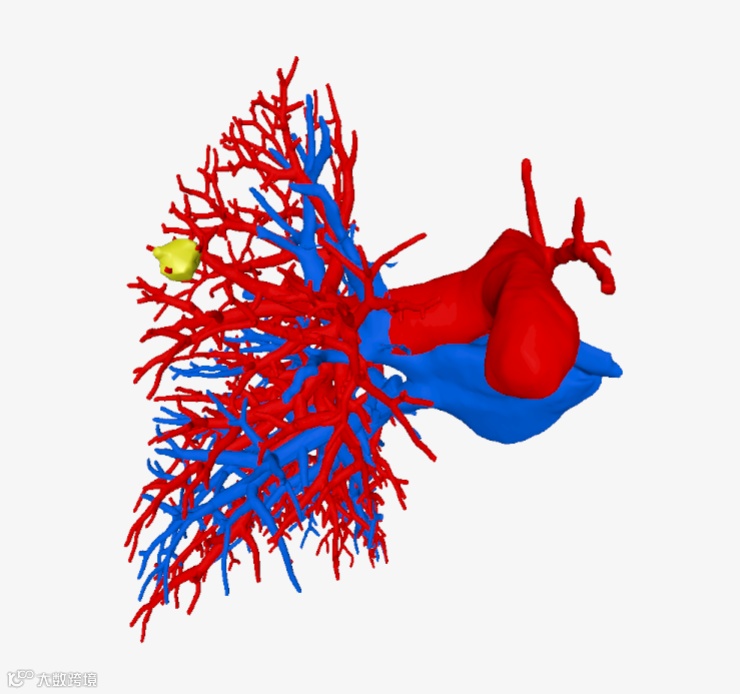

▲▲▲三维重建血管

该院胸外科手术团队用瀚依科技的AI三维重建服务,真实还原了结节的大小、位置和深度,全方位、多维度地观察了患者结节的空间位置、结节与周遭脏器粘连程度、结节对血管的侵占情况,并对手术需要的重要信息进行精准定量分析。

▲▲▲局部细节